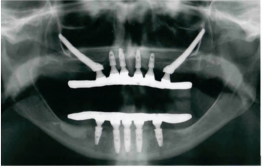

Observe a panorâmica de um paciente edêntulo total.

Caracteriza-se a reabilitação apresentada na imagem, no que concerne à prótese, conexão e implante utilizados como: